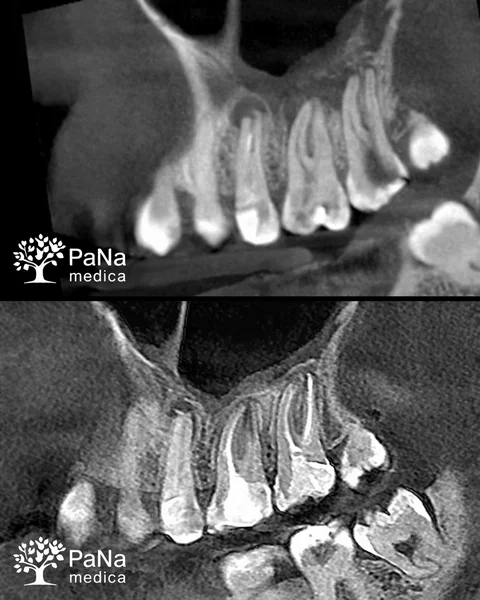

Usuwamy złamane fragmenty narzędzi

Czasami trafiają do nas pacjenci z sytuacjami, które już uznaje się za „trudne” — na przykład kiedy w kanale został złamany fragment narzędzia po wcześniejszym leczeniu. W takich przypadkach często mówi się, że jego usunięcie jest praktycznie niemożliwe.

Ale w praktyce nie zawsze tak jest.

Dzięki pracy pod mikroskopem i doświadczeniu naszych lekarzy jesteśmy w stanie dokładnie zlokalizować i usunąć takie fragmenty, zachowując ząb i unikając zbędnych ingerencji. Dla nas to nie jest sytuacja awaryjna, tylko konkretne zadanie, które potrafimy wykonać spokojnie i precyzyjnie.